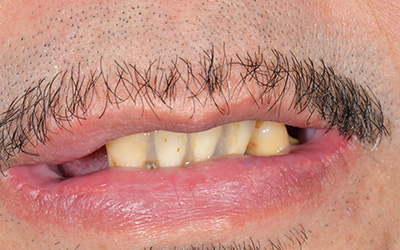

【歯周病で多数歯欠損③】【職業:俳優】芸能人は歯が命 膿が出て歯がぐらつくことで食事が怖くコンプレックスだった口元から自信をもって笑える長所へ

患者さま情報:40代 男性

治療期間:1年

治療費:4,082,100円(税込)

リスク:歯茎がない場合、移植を行う場合があります。

副作用:術後の痛みは投薬で抑えられたが、腫れは見られた

before